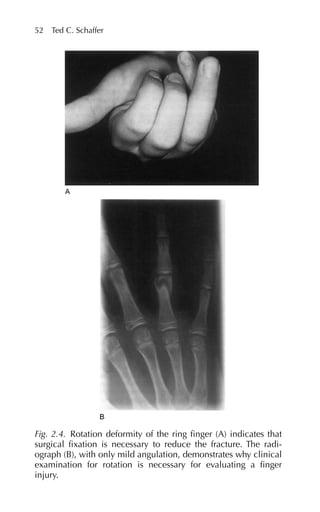

The diagnosis canbe confirmed radiographically if there is evi- dence of sacroiliitis. If the disease has progressed, patients have the “bamboo spine” seen on radiographs. The ESR is elevated. It is easy to measure the flexibility of the spine, which is decreased in most patients. The two most commonly used tests to assess spinal flexion are Schober’s flexion test and Moll’s lateral flexion test. Schober’s test is performed by identifying, with the patient standing, the top of the sacrum and marking on the spine points 10 cm above this point and 5 cm below. In normal individuals, with forward flexion this dis- tance increases by at least 5 cm. The Moll’s lateral flexion test is per- formed by marking the point in the midaxillary line of the iliac crest and the point 20 cm above this site. When the normal patient bends to the opposite side, this distance increases by at least 3 cm.33 The goals of treatment of ankylosing spondylitis are to decrease pain and maintain functional status. NSAIDs are the drugs of choice to control inflammation and decrease pain. Oral prednisone has not been shown to be helpful. It is also important in the preservation of functional status to encourage the patient to strengthen back extensor muscles. At the present time, spinal ossification cannot be prevented, but function is better preserved if the patient’s spine is ossified in an erect position in contrast to stooped over. Psoriatic Arthritis Psoriatic arthritis is a form of inflammatory arthritis seen in approxi- mately 20% of psoriasis patients (see Reference 37, Chapter 115). Like ankylosing spondylitis, patients with psoriatic arthritis have serum negative for rheumatoid factor. Psoriatic arthritis is usually a mild form of arthritis that is sometimes difficult to distinguish from rheumatoid arthritis. Points for differentiating psoriatic arthritis from rheumatoid arthritis are as follows. Psoriatic arthritis is found in patients with psoriasis, distal joint involvement, tenosynovitis, and enthesopathy. Psoriatic arthritis is generally treated with NSAIDs or antimalarials. In up to one third of patients a flare in the skin disease may precede a flare of joint symptoms.34 Polymyalgia Rheumatica Patients with polymyalgia rheumatica are usually over age 50 and present with complaints of myalgias and arthralgias referable to the hips and shoulders. The pain usually has been present for several 122 Joseph W. Gravel Jr., Patricia A. Sereno, Katherine E. Miller

• 137.

months, and patientsmay suffer from constitutional symptoms including fatigue, weight loss, and low-grade fever. Patients complain that these muscles or joints are achy, and that they have morning stiff- ness. Polymyalgia rheumatica has a prevalence of approximately 1 in 150 persons over age 50.35 On clinical examination, patients are ten- der to palpation, but their strength is intact and creatine phosphoki- nase levels are normal, ruling out muscle destruction. The most characteristic finding in polymyalgia rheumatica is an elevated ESR. In fact, many patients have ESRs in excess of 100 mm/hr. It is esti- mated that one fourth to one half of patients with polymyalgia rheumatica also have temporal arteritis. Some patients with polymyalgia rheumatica respond to NSAIDs, but the key to treatment has traditionally been a prolonged course of a corticosteroid. Patients generally respond quickly to prednisone at a dose of 10 to 20 mg/day. If a patient does not respond quickly to cor- ticosteroids, consider other diagnoses. Patients often require daily steroids for a minimum of two years. When attempts are made to wean a patient off prednisone, the dose is decreased by only 1 mg/ month. Temporal Arteritis Temporal, or giant cell, arteritis, like polymyalgia rheumatica, pres- ents in persons over 50 years of age with an annual incidence 18/100,000 people over age 50. It is more common among the Caucasian population but has been reported in nonwhite patients; it occurs more commonly in women with a female/male ratio of 3:1. Most patients present with headache and may have tenderness to pal- pation over the temporal artery (see Reference 37, Chapter 63). Patients may also have visual symptoms including diplopia, hemi- anopia, or amaurosis fugax (visual changes usually described as a window shade being pulled down over one eye). As with polymyalgia rheumatica, patients with temporal arteritis usually have an elevated ESR to levels higher than 100 mm/hr; con- firmation of this diagnosis requires biopsy of the temporal artery. Biopsy results are more likely to be positive if specimens are obtained less than 24 hours after beginning treatment. It is recommended not to withhold treatment pending biopsy results in patients with a high clin- ical suspicion because of the risk of blindness. Patients are started on prednisone 1 mg/kg/day, and the dosage is decreased based on symp- toms and the ESR.36 5. Rheumatoid Arthritis and Related Disorders 123